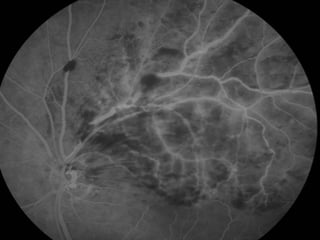

Angiografia 10/02/2009

Caso Clínico

• ANGIOGRAFICO

– Define edema macular, a perfusão da rede capilar para-foveal e a presença de

neovasos.

– Mostra o retardo artério-venoso na arcada comprometida e a presença de

áreas isquêmicas e de vazamento tardio.

Caso Clínico Exame Oftalmológico: AcuidadeVisual c/c: • OD = 20/20 • OE = 20/100 (metamorfopsias) • Add: +3,00 Biomicroscopia: Normal FO: OD: Normal. OE: Hemorragias retinianas temporal superior. Edema Macular Solicitado: Angiografia e OCT